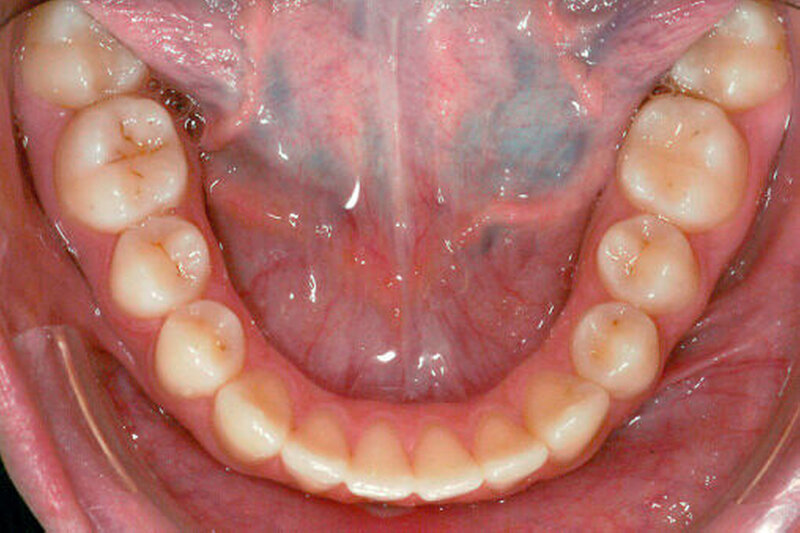

Die Patientin stellte sich im Jahr 2007 im Alter von elf Jahren erstmals zur kieferorthopädischen Beratung in der Klinik für Kieferorthopädie der Medizinischen Hochschule Hannover vor. Extraoral konnten in der Profilansicht eine mandibuläre Retrognathie mit ausgeprägter Supramentalfalte sowie in der En-Face-Ansicht ein runder Gesichtstyp diagnostiziert werden. Intraoral wies die Patientin ein spätes Wechselgebiss auf. Röntgenologisch zeigte sich die Anlage der Zähne 17 bis 47, wohingegen die Anlage der Weisheitszähne nicht abschließend beurteilt werden konnte. Die Mundhygiene der Patientin war verbesserungswürdig, die marginalen Parodontien zeigten sich entzündungsfrei.

Die Auswertung der zu Behandlungsbeginn erstellten diagnostischen Unterlagen (Modelle des Ober- und des Unterkiefers, Orthopantomogramm, Fernröntgenseitenbild, extra- und intraorale Fotos, siehe Abbildung 1) ergab folgenden Befund:

Der Befund lautete: Dysgnathie der Angle-Klasse II, Transposition von 22 und 23, Hypoplasie von 12 und 22.

Die Patientin und deren Eltern wurden über die verschiedenen Versorgungsmöglichkeiten der Zähne 12 und 22 zur Rekonturierung und zur Verringerung der verbleibenden Lücken im Frontzahnbereich nach Abschluss der kieferorthopädischen Behandlung wie zum Beispiel direkte Kompositrestaurationen, Komposit- beziehungsweise Keramikveneers oder Frontzahnkronen, aufgeklärt. Da die Patientin ein kariesfreies Gebiss aufwies und möglichst Zahnhartsubstanz-schonend therapiert werden sollte, wurde eine Versorgung mit direkten Kompositrestaurationen gewählt. Aufgrund einer mangelnden Mundhygiene und einer daraus resultierenden plaqueinduzierten Gingivitis mit ausgeprägter Gingivahyperplasie (siehe Abbildung 2a) konnte ein adhäsiver Aufbau der seitlichen Schneidezähne und des Zahnes 23 erst nach der Entfernung der Multibracket-Apparatur und erfolgreicher Therapie der Gingivitis in Form von Mundhygienesitzungen und regelmäßigen Recalluntersuchungen erfolgen (siehe Abbildungen 2b und 2c). Es kann manchmal sinnvoller sein, den Aufbau bei in situ befindlicher Multibracket-Apparatur durchzuführen, um später noch etwaige Feinkorrekturen vornehmen zu können.